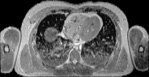

Visible Human male: Sectio transversalis 1459

CT

NMR

Pd                          / T2 \                         T1